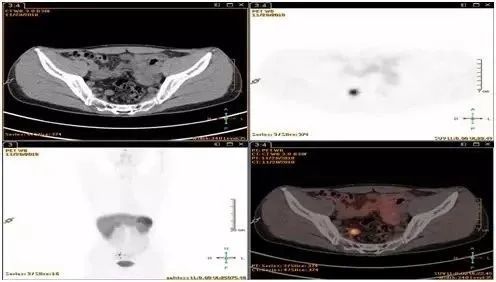

68镓-PET-CT或奥曲肽扫描么?

答:直径小于1 cm,CT或MRI检查无可疑转移病灶的,可以不做;直径超过1 cm,CT/MRI等影像检查有可疑结节或病灶的需要做。

图片